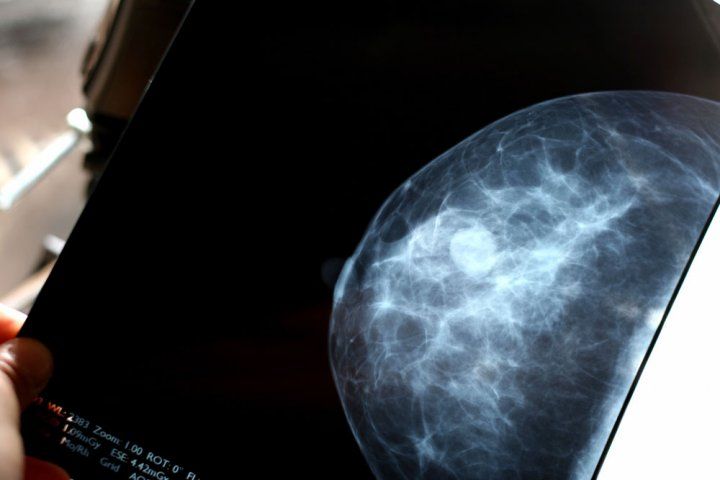

Breast scan.